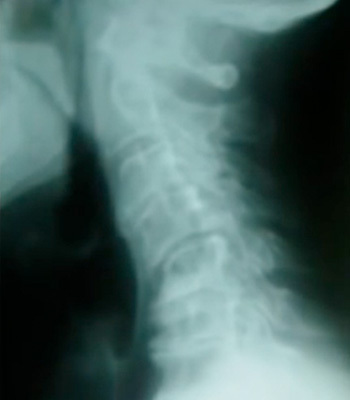

ストレートネックが何年も経過した頚椎

(肩こり、重度頭痛、手の痺れなど)

初期や症状が無い場合は、首のストレッチや柔軟体操などをコツコツ行なうことで頚椎のカーブが戻ってくることも多いですが、症状がありストレートネックが酷くなって後湾している場合は頸椎が変形する前に体全体のバランスを整え頸椎の歪みを調整をしていくことが大切です。